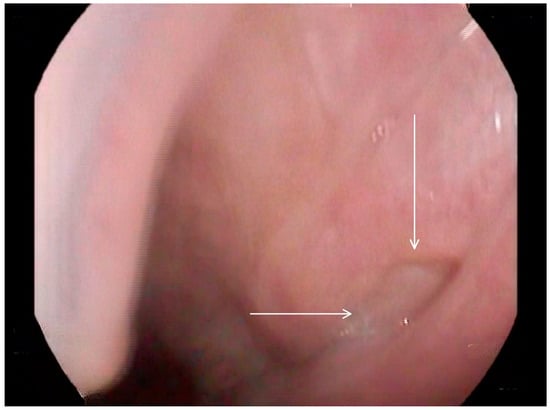

The FEES procedure was conducted with different consistencies of liquid and purée of 1 mL, 3 mL, 5 mL, and 10 mL applied with a teaspoon and a tablespoon. The results indicated the following:

• Oropharyngeal dysphagia characterized by the following features: flaccid uvula and delayed swallowing trigger at the level of the vallecular with thin liquid, thick liquid, and puree.

• Deep residue in vallecular and pyriform sinuses with all the consistencies (suggestive of a vallecula pouch), and signs of reflux.

• No aspiration or penetration with all the consistencies was observed during the study.

Following these findings, the ENT specialist reassessed the patient and confirmed the presence of bilateral diverticula in the buccal area and posterior pharyngeal walls, in alignment with the VFSS findings. The two diverticula were located on the right and left side inferiorly in the buccal area (Figure 3) and (Figure 4), and two were located on the right and left side superiorly in the oropharynx area. (Figure 5) and (Figure 6).

Figure 3. Selected still image captured during the FEES assessment: arrow heads pointing to the opening of a diverticulum located in the left inferior aspect of the buccal area.

Medicina 60 01628 g003

Figure 4. Selected still image captured during the FEES assessment: arrow heads pointing to the opening of a diverticulum located in the right inferior aspect of the buccal area.